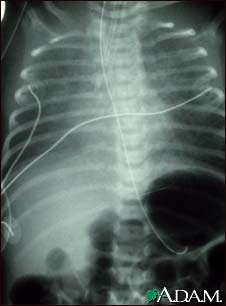

Totally anomalous pulmonary venous return (TAPVR) is a form of congenital heart disease. This x-ray shows an enlarged heart, a large liver, and increased pulmonary vascularity.